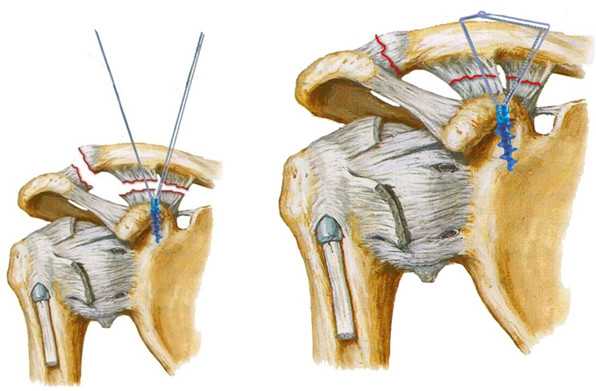

Всем пациентам была выполнена оперативная реконструкция ключично-клювовидной связки и трансартикулярная фиксация АКС. В ходе операции проводилась резекция фиброзной ткани, удаление интерпонента, мениска и рубцов из полости сустава. Для восстановления ключично-клювовидной связки применялась малоинвазивная (пуговичная) методика, позволяющая через минимальный доступ в проекции сустава, после выполнения полноценного дебридменда, выполнить ее реконструкцию. Под интраоперационным рентгенологическим контролем выполнялось пе Предложенный подход к лечению пациентов с застарелыми травматическими вывихами акромиального конца ключицы продемонстрировал хорошие функциональные результаты. Через 2 месяца с момента операции, большинство ( 25 из 27 случаев) оперированных нами пациентов вернулись к привычному образу жизни, а спустя еще 2 месяца они имели возможность приступить к спортивным нагрузкам. Разработанный протокол лечения позволил получить более чем в 90% случаев полное восстановление функции, из- бежать повторных оперативных вмешательств и серьезных хирургических осложнений. На контрольных рентгенограммах, выполненных через 6 месяцев после операции и позднее отмечается правильное соотношение костей в АКС и стабильность фиксатора. При использовании визуально-аналоговой шкалы выявлен хороший результат (0-3 балла) у 92,6% пациентов. ркутанное трансартикулярное введение 2-х спиц через акромиальный отросток лопатки в акромиальный конец ключицы. Последующие 6 недель пациентам предписывалась иммобилизация руки в ортезе типа Дезо. Удаление спиц выполнялось на 4-ой неделе с момента операции.

На восьмые сутки с момента травмы пациенту выполнена операция: открытое вправление вывиха правой ключицы и фиксация правого акромиально-ключичного сустава малоинвазивной «пуговичной» системой и 2-мя спицами трансартикулярно под контролем эОП (рис. 2). В ходе операции из доступа около 3-х см выполнен полноценный дебридмент околосуставной области, а также удаление рубцовых интерпонентов из полости акромиально-ключичного сустава.